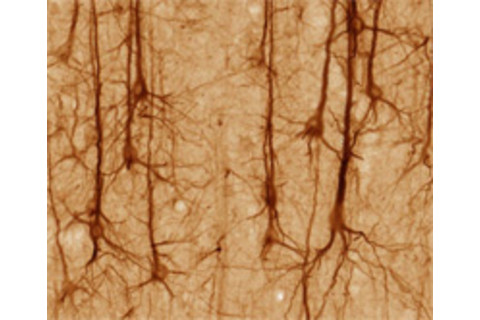

Han 发现一种叫做 CREB 的蛋白质是一种分子信标,它可以识别与恐惧经历记忆相关的神经元。当老鼠经历可怕的事情时,大脑杏仁核区域的 CREB 神经元负责存储该记忆——产生神经科学家称之为“痕迹”的东西。当 Han 杀死杏仁核的 CREB 神经元时,他触发了小鼠的选择性遗忘症,消除了它们被训练出来的特定恐惧。记忆丧失是永久性的。

这是一项重要的工作。科学家们一直认为记忆是由特定的神经元集合代表的。但这些神经元并非整齐地聚集在一起;它们通常分散得很广,这使得寻找构成任何特定记忆的细胞变得极其困难。Han 通过使用 CREB 蛋白作为标记物来完成这一点。通过这样做,他突出了这种蛋白质在我们记忆中的重要作用。

此前,Han 的研究表明,杏仁核中的神经元会根据它们含有的 CREB 量 被募集形成新的记忆痕迹。他增加了少量神经元中这种重要蛋白质的含量,并发现与正常邻居相比,当他训练老鼠对音乐音调产生恐惧时,这些 CREB 增强的细胞被激活的可能性要高出三倍。而完全缺乏 CREB 的神经元在老鼠学会恐惧时被激活的可能性要低 12 倍。

当病毒感染随机的小鼠神经元时,它会产生 CREB 和 Cre。后者激活白喉受体的基因。这个系统意味着任何含有高水平 CREB 的神经元也会容易受到白喉毒素的影响。利用这种毒素,Han 能够只杀死那些含有 CREB 的神经元,而让所有其他神经元不受伤害。这意味着最有可能被整合到恐惧记忆痕迹中的神经元也变得容易被一举消灭。这是一个构建精美的设置,展示了现代生物技术的强大和优雅。